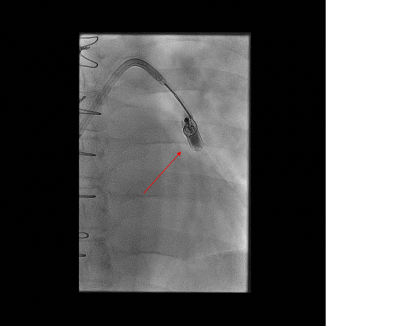

Dalším krokem byla explantace leadless systému. Po punkci pravé femoralní žíly byl zaveden řiditelný sheath (Agilis, St. Jude Medical, St. Paul, MN, USA), který nám umožnil manipulaci v pravé komoře a ve výtokovém traktu pravé komory. K samotné explantaci byla použita jednooká zachycovací klička („single-loop gooseneck snare“, COOK Medical, Bloomington, IN, USA), která byla pod skiaskopickou kontrolou navigována do větve pulmonální arterie, kde byl lokalizován uvolněný kardiostimulátor. Systém byl zachycen a stažen (obr. 2, 3). Samotné vyjmutí kardiostimulátoru bylo provedeno po předchozí cévně-chirurgické přípravě s venotomií femorální žíly.